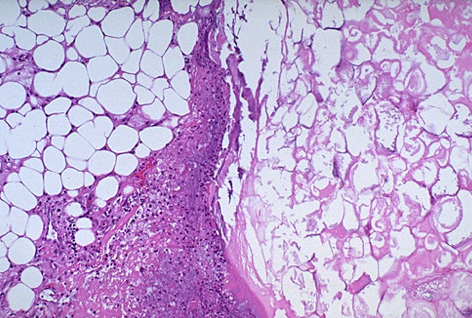

Hist:

• Edema by microvascular leakage

• Fat necrosis by lipolytic enzymes (saponification)

• Acute inflammation (neutrophils)

• Proteolytic destruction of pancreatic parenchyma

• Destruction of blood vessels and subsequent interstitial hemorrhage

Pic shows Fat necrosis with dystrophic calcifcation